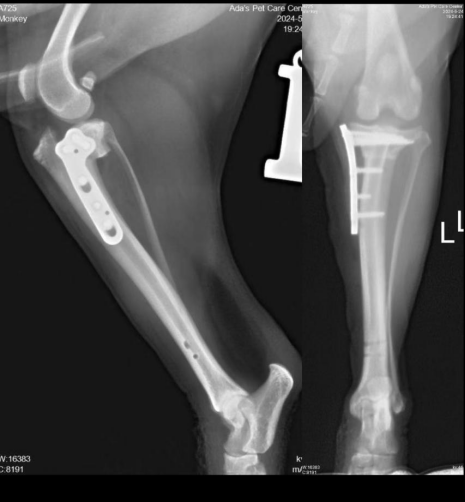

由于狗狗在清醒状态下无法进一步进行检查,孙医生决定进行镇静麻醉。通过镇静后,详细检查中发现左后肢的抽冠试验呈阳性,明确提示前十字韧带断裂。同时,膝关节的X光检查显示在受力状态下,股骨和胚骨处于半脱位状态。最终确诊为左后肢前十字韧带断裂。